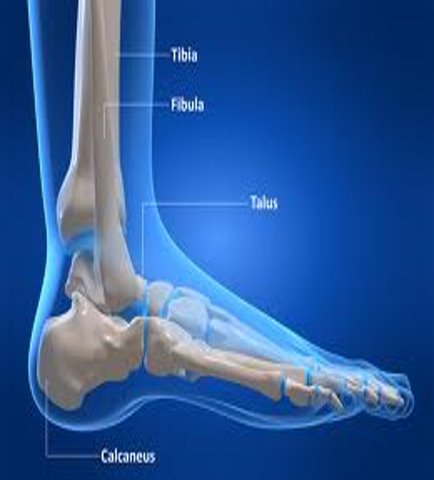

The ankle joint resembles a pincer or monkey wrench grasping a portion of hemisphere.

48+ Mri Anatomy Of Ankle Joint Ppt. 6 ankle and foot joints talocrural joint (ankle) uniaxial hinge subtalar joint gliding/nonaxial transverse tarsal joints intertarsal joints tarsometatarsal joints metatarsophalangeal joints biaxial ball and socket proximal interphalangeal joints little toes.  tibia, fibula & talus form synovial joint.

The mri ankle protocol encompasses a set of mri sequences for the routine assessment of the ankle joint. This is the strongest largest bone of the lower leg. The ankle joint is also supported by nearby tendons. The ankle supports the weight of anatomy ▶ lower limb ▶ joints and ligaments ▶ ankle joint (talocrural joint).